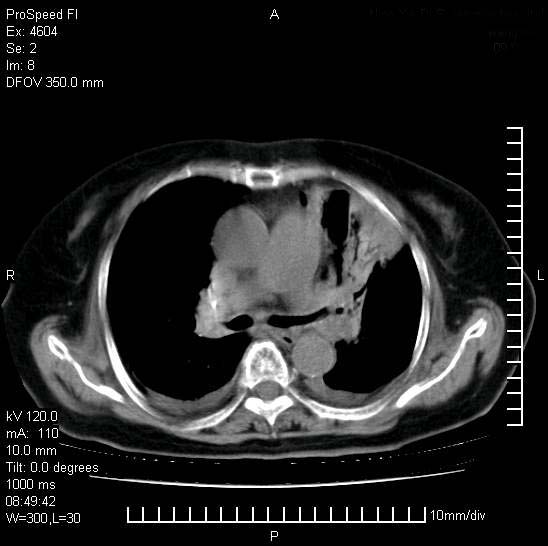

十几年前曾患肺结核,一周前突咳血约100ml,中性粒细胞稍高,诊断两上肺陈旧结核,下肺炎症,给予抗炎治疗,近几日晚上高热,39度,仍咳少量血,4天前ct及今天ct上传。

[face=黑体]8月30日[/face]

今天ct

支持陈旧性肺结核并两下肺感染,两侧胸腔积液。

短短几天内,病变范围明显增多扩大,以左侧明显,而且双侧出现胸水,还是考虑感染.

短短几天内,病变范围明显增多扩大,以左侧明显,而且双侧出现胸水,我更多考虑左侧中心性肺癌并并阻塞性不张及肺炎,炎症变化也太快了!

1)两肺结核并感染。2)不排除左肺上叶中央型肺癌并阻塞性肺炎、肺不张可能;建议行纤支镜检查。3)右肺门及纵隔淋巴结肿大。4)双侧胸腔积液。

陈旧性肺结核及左下肺不张,咯血后肺部感染,双胸腔积液,高热可能与痰液引流不畅有关。